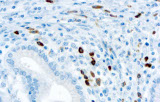

- Assegnazione del lignaggio & principali diagnosi differenziali: Fenotipizzazione cellule B vs cellule T (es. CD20 vs CD3), supportata da fattori di trascrizione nucleari delle cellule B come PAX5 quando i marcatori pan-B sono deboli/assenti.

- Linfoma di Hodgkin classico: le cellule tumorali sono tipicamente CD30+ e spesso CD15+, con PAX5 debole e CD20 negativo nelle grandi cellule tumorali.